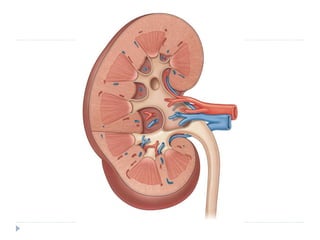

-Both grossly and microscopically there are two distinct

components within the renal the parenchyma: the

:medulla and the cortex

-Unlike the adrenal gland, the renal medulla is not a

contiguous layer. Instead, the medulla is composed of

multiple, distinct areas noticeably darker in color than

the cortex . These same structures are also

frequently called renal pyramids, making the terms

renal medulla and renal pyramid synonymous.

The apex of the pyramid is the renal papilla,and each

papilla is cupped by an individual minor calyx.

-The renal cortex is lighter in color than the medulla and not

only covers the renal pyramids peripherally but also

extends between the pyramids themselves. The

extensions of cortex between the renal pyramids are

given a special name: the columns of Bertin.

Renal Papillae, Calyces, and Pelvis

-The renal papillae are the tip of a medullary pyramid

and constitute the first gross structure of the renal collecting

system.

-Each of these papillae is cupped by a minor calyx.

-After cupping an individual papilla, each minor calyx

narrows to an infundibulum.

-Infundibuli combine to form two or three major calyceal branches.

These are frequently termed the upper, middle, and lower pole

calyces, and

these calyces in turn combine to form the renal pelvis.

-The renal pelvis itself can vary greatly in size, ranging from a small

intrarenal pelvis to a large predominantly extrarenal pelvis.